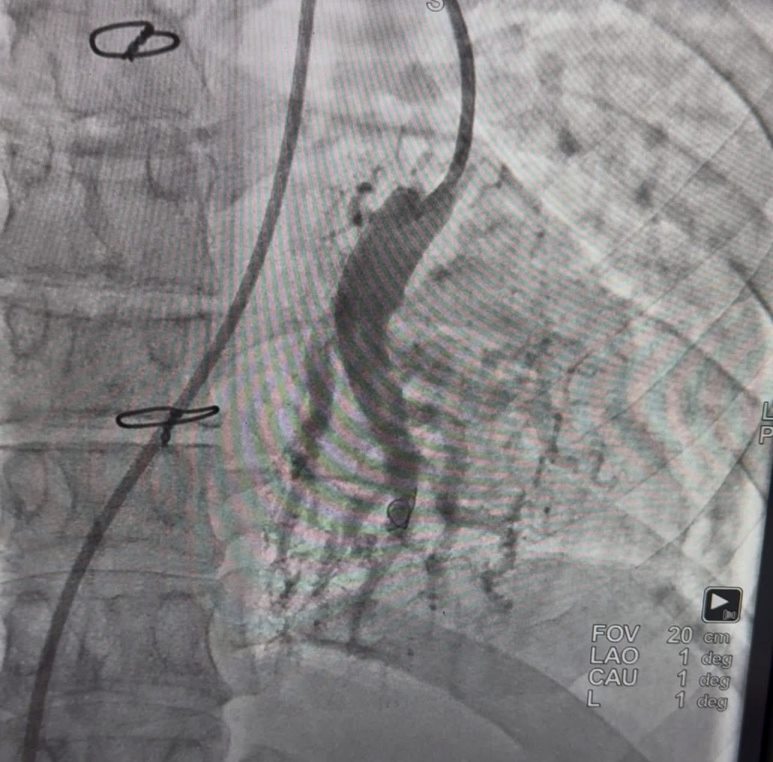

15 травня 2025 року в КНП «Дрогобицька міська лікарня №1» відбулася знакова подія: лікарі закладу спільно з польським кардіохірургом успішно провели балонну ангіопластику легеневих артерій молодому пацієнту з важкою формою хронічної тромбоемболічної легеневої гіпертензії. Про це повідомили у медустанові. Це — перша така операція у західному регіоні Україні.

“Команда у складі Мар’яни Лепкої, Яцека Пеґзи та Василя Романяка виконала легеневу ангіопластику 33-річному пацієнту з хронічною тромбоемболічною легеневою гіпертензією на пізній стадії. У такій важкій стадії захворювання у нелікованих пацієнтів 5-річний ризик смерті становить 90%”, – розповіли у медустанові.

Балонна ангіопластика легеневих артерій — складна високотехнологічна процедура, яку застосовують у лікуванні пацієнтів із важкими порушеннями легеневого кровообігу. Успішне проведення такої операції — важливий крок у розвитку інтервенційної кардіології в регіоні та ще один доказ високої кваліфікації місцевих лікарів.